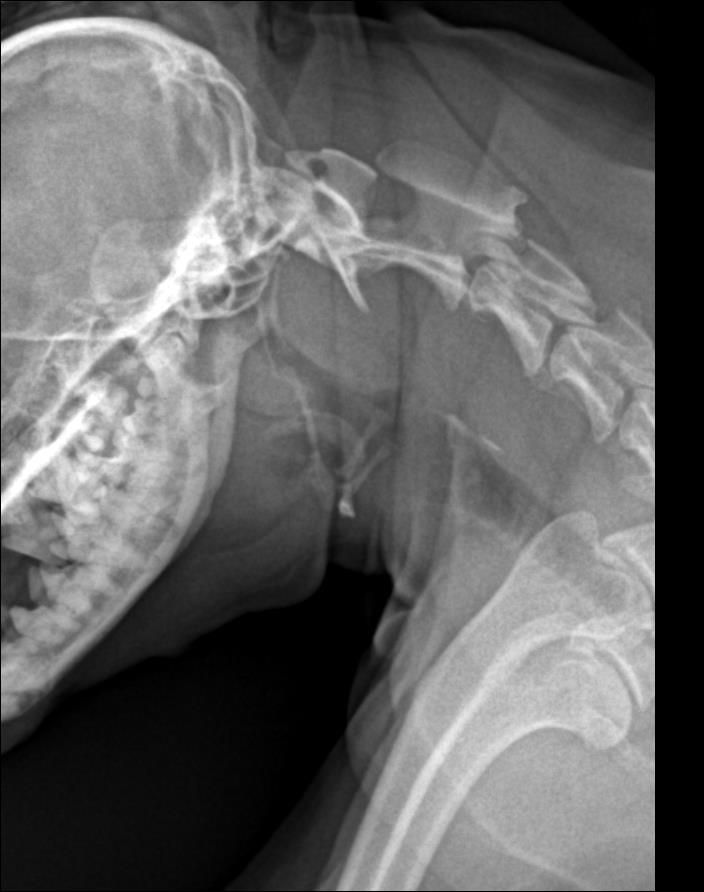

경추 4-5-6번의 추간판 사이가 좁아보이며 동시에 복부 방사선 촬영 시 결장에 가스가 많이 차 있는 것을 볼 수 있습니다.